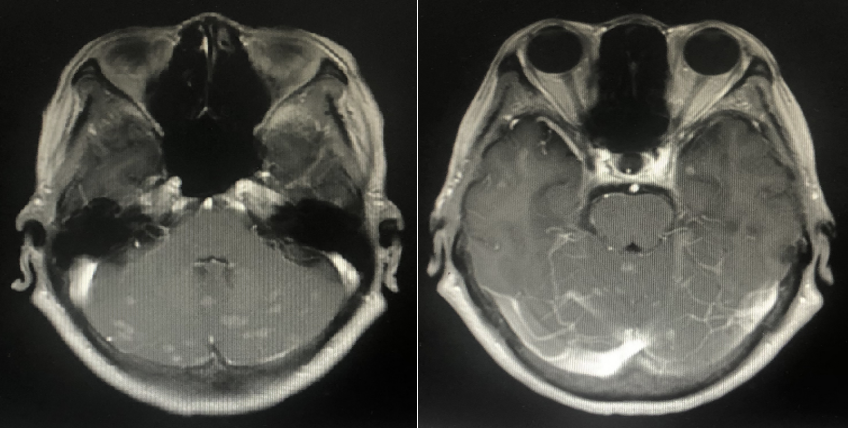

2022年10月头颅MR:脑内多发异常强化灶,结合病史考虑转移。(新发脑转移)

二线治疗方案:吡咯替尼 400mg/d + 卡培他滨 1.0g 2次/d 1/21d(依据PHENIX研究)

PHENIX研究:基线有脑转移患者,吡咯替尼方案可延长中位PFS近3月,有效抑制脑转移进展。

疗效评估:PR

2023年9月头颅增强MR:脑内多发异常强化灶,部分较前缩小。

二线PFS:19月